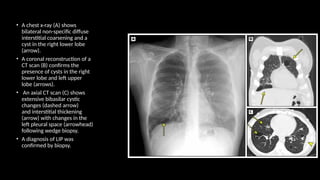

• Computed tomography (CT) features: (A)Axial and (B) coronal CT show confluent bilateral lower

lobe ground glass opacities with marked traction bronchiectasis and

lower lobe volume loss.

• The peribronchovascular predominance with subpleural sparing is well shown on the axial image.

Bilateral, peribronchovascular

ground glass attenuation

Traction bronchiectasis

A relative subpleural sparing

No honeycombing

• Computed tomography(CT) features: (A)Axial and (B) coronal CT show confluent bilateral lower lobe ground glass opacities with marked traction bronchiectasis and lower lobe volume loss. • The peribronchovascular predominance with subpleural sparing is well shown on the axial image.

Bilateral, peribronchovascular ground glassattenuation Traction bronchiectasis A relative subpleural sparing No honeycombing